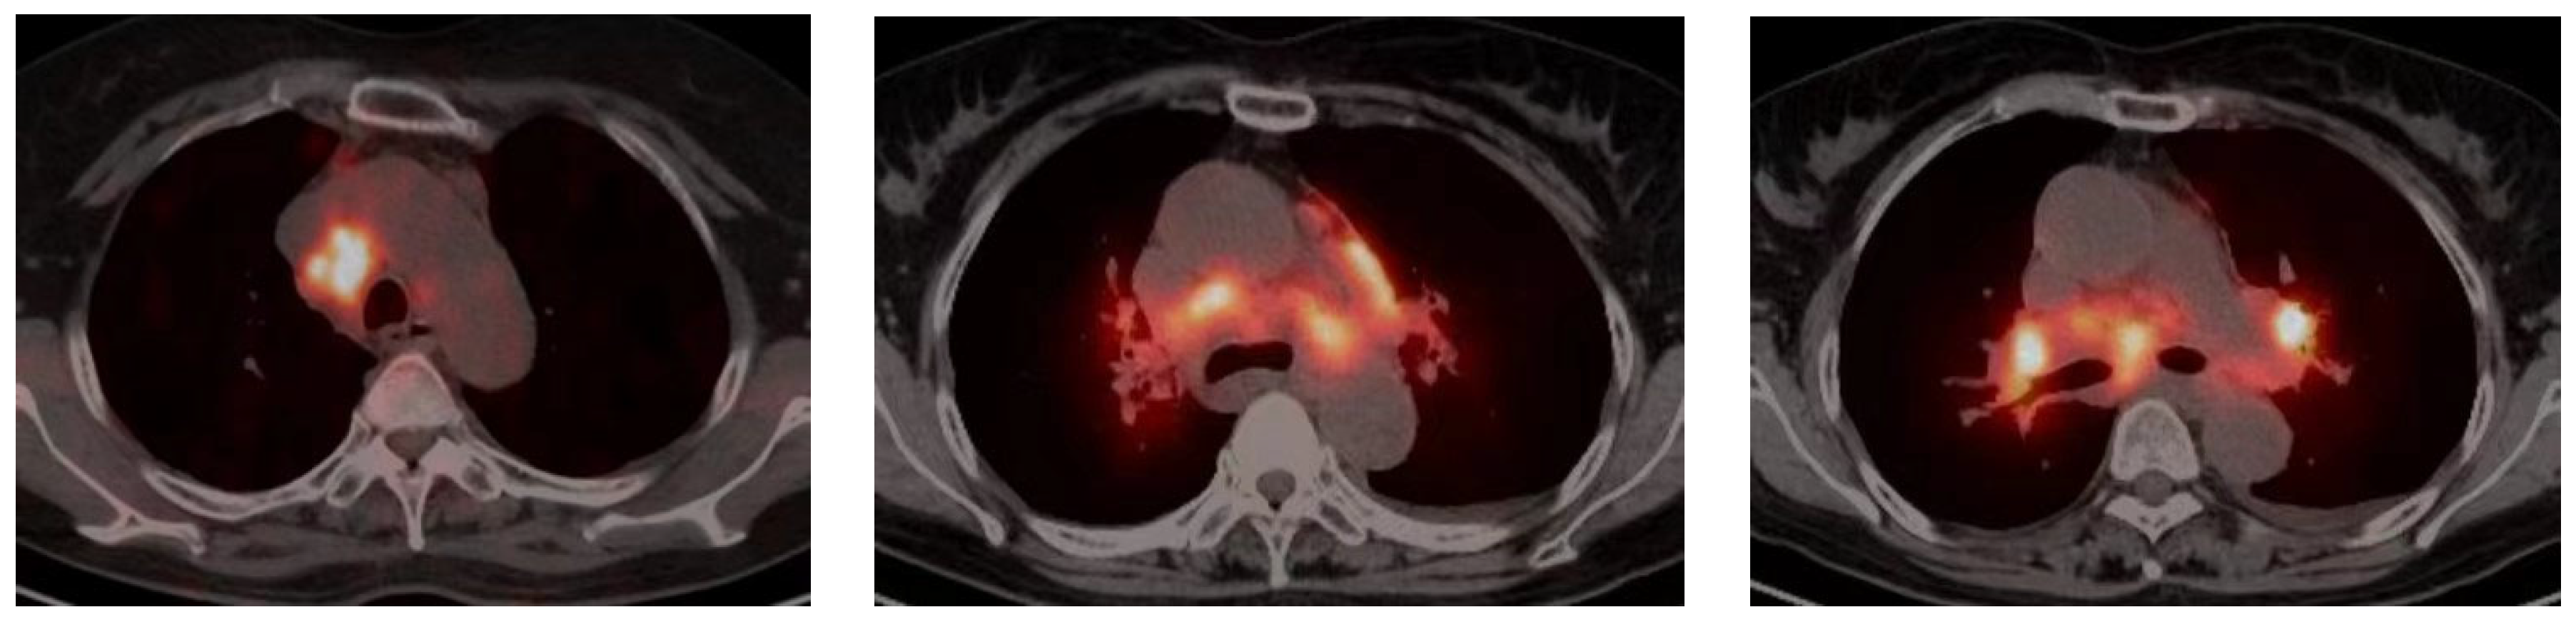

2.3. Fluorodeoxyglucose Positron Emission Tomography/Computed Tomography (FDG-PET/CT)

- Regis, C.; Benali, K.; Rouzet, F. FDG PET/CT Imaging of Sarcoidosis. Semin. Nucl. Med. 2023, 53, 258–272. [Google Scholar] [CrossRef]

| FDG-PET CT | Spinal cord sarcoidosis | mean SUV: 4.38 (3.30–4.93) higher than 1.87 (1.42–2.74) | 0.02 | Myelomalacia |